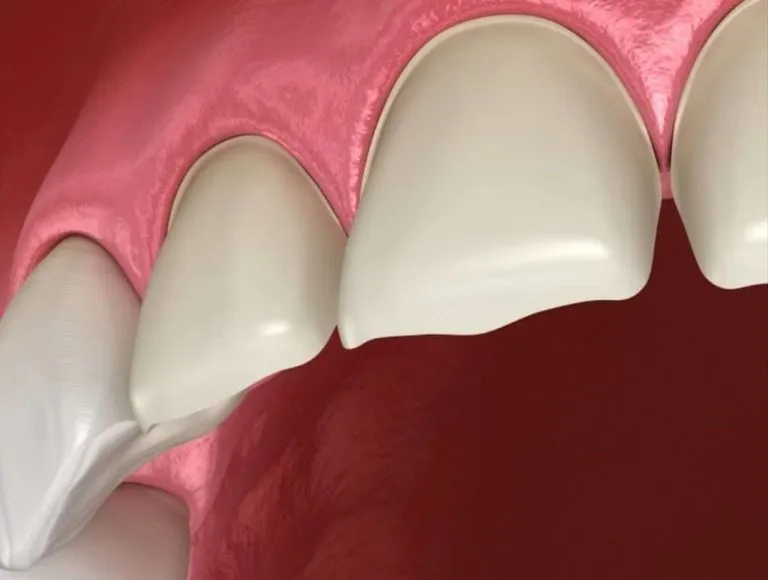

A oclusão dentária exerce influência direta sobre a função mastigatória, a estabilidade do tratamento ortodôntico e a saúde do sistema estomatognático como um todo. Na prática